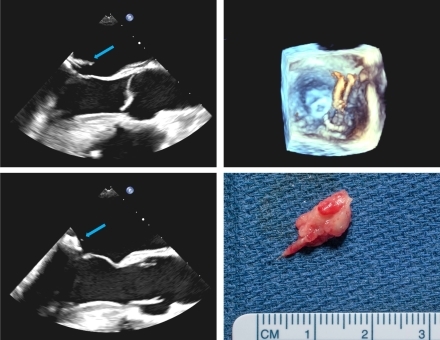

Transesophageal echocardiogram revealed mobile mitral valve vegetations up to 1.8cm on the atrial aspect of the posterior mitral valve leaflet which prolapsed through the mitral valve during diastole. Ejection fraction was 60% and there was trivial-mild mitral regurgitation without valvular destruction or peri-annular extension into the mitral annulus. MRI brain showed bilateral cerebral and cerebellar hemispheric infarcts, consistent with acute embolic stroke.

He was at high risk for both recurrent embolism and operative mortality (STS risk score 51%) due to his comorbidities and risk of hemorrhagic conversion of stroke. After shared decision making, percutaneous aspiration of the mitral vegetation was performed with AngioVac (Fig). Cerebral embolism protection devices were deployed prior to AngioVac evacuation of the mass.

There was no residual mitral regurgitation and only a small vegetation strand remained (Fig). Surgical pathology confirmed MSSA endocarditis. Blood cultures remained negative, and the patient did not suffer from recurrent embolic events. The patient underwent revision metatarsal amputation and was discharged with a 6-week course of IV cefazolin.